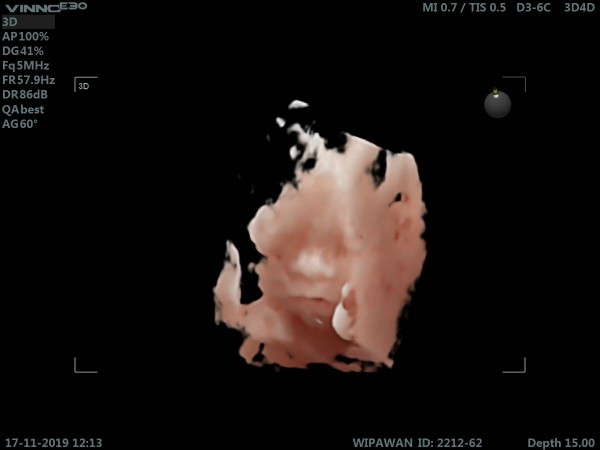

บ้านนี้ชัดครับผม

ซาวด์ตอน 31 w จร้าา